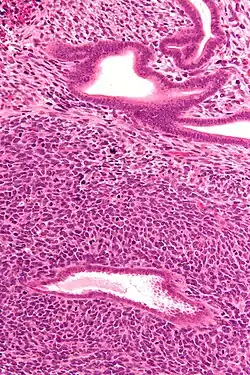

| Micrograph of a uterine adenosarcoma showing a mitotically active malignant stroma and benign glands. H&E stain. | |

Uterine adenosarcoma have, by definition, a malignant stroma and benign glandular elements. The World Health Organization (WHO) criteria have a mitotic rate cut point; however, this is often disregarded, as bland-appearing tumours with a low mitotic rate are known to metastasize occasionally.[2]